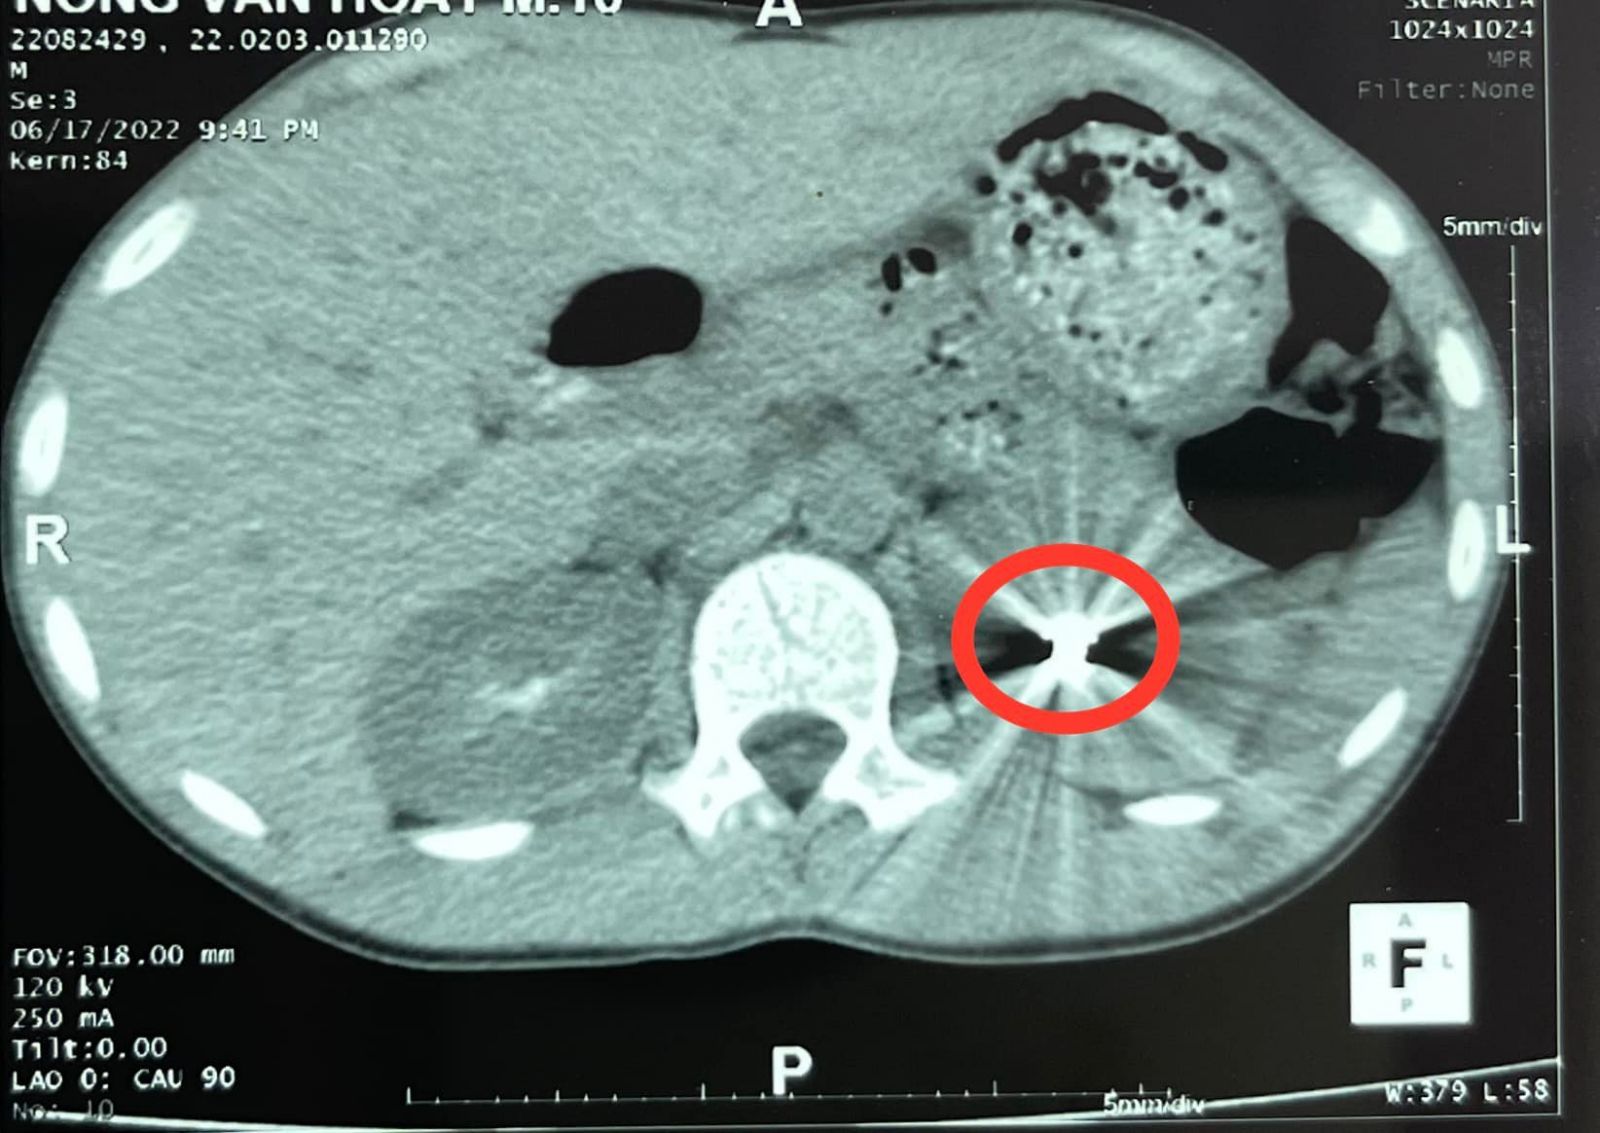

Sau khi được siêu âm, chụp CT bụng có cản quang đã phát hiện dị vật hình viên đạn trong thận trái, bệnh nhân được chuyển đến Khoa Ngoại thận tiết niệu nam học. Tại đây, các bác sĩ đã nhanh chóng hội chẩn và kết luận: bệnh nhân có vết thương thận trái cho đạn bắn, chỉ định mổ cấp cứu lấy dị vật và khâu bảo tồn thận. Kíp mổ do BsCKII Đoàn Tiến Dương, Trưởng khoa Ngoại thận tiết niệu nam học mổ chính. Ekip phẫu thuật đã thực hiện rạch vết thương thận, lấy viên đạn súng hơi ra ngoài, khâu cầm máu vết thương, làm sạch khoang quang thận đồng thời truyền 500ml máu trong cả quá trình phẫu thuật. Sau 1 giờ đồng hồ, ca phẫu thuật đã thành công, sinh tồn bệnh nhân ổn định, đầu đạn chì kích thước 0,4cmX0.7cm đã được lấy ra ngoài.

*Một số hình ảnh trong quá trình điều trị: